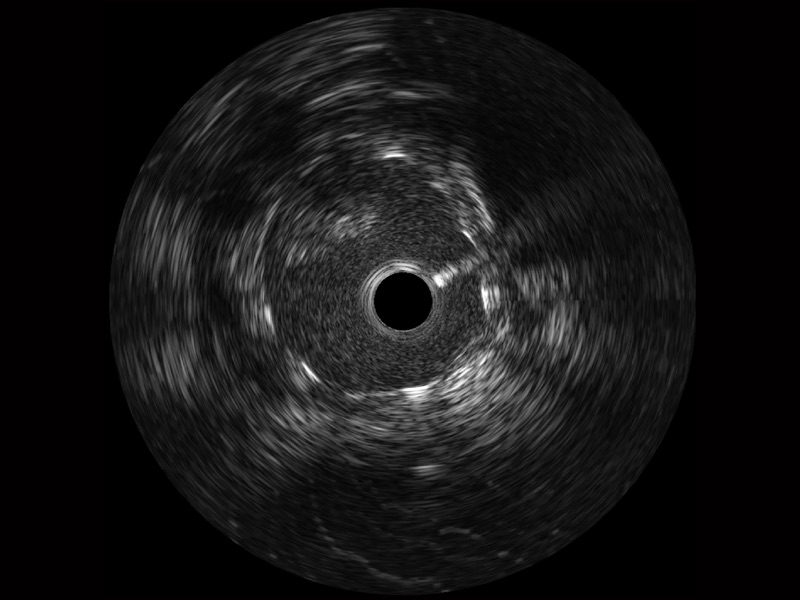

环球UG官网宽频IVUS图像

对比传统IVUS导管成像,环球UG官网宽频IVUS图像的近场支架梁显影更细腻,远场中膜外血管仍清晰可辨,兼顾远中近,兼顾分辨力与穿透深度